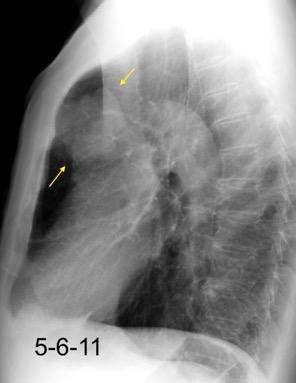

De los pacientes con Tumor de Pancoast

1,7% tienen una radiografía de tórax normal

Fletcher F et al. The normal chest radiograph in bronchial carcinoma. Br Med J. 1976